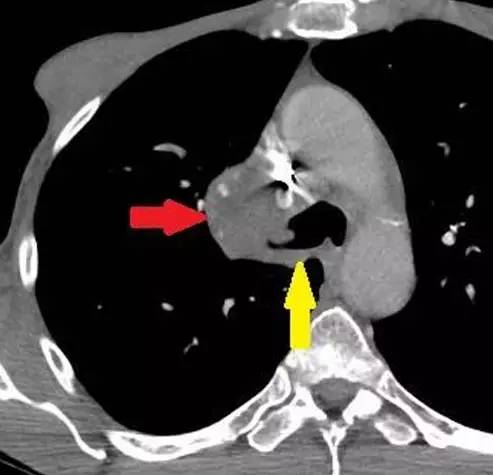

图 2. 横断增强 CT 示一巨大中央型肿块(红色箭头),并侵入右侧主支气管(黄色箭头)

「反 S」征指的是右肺上叶膨胀不全,水平裂向上移位,右肺门肿块共同形成胸片上反 S 形的凸出影。肺癌是引起「反 S」征最常见的病因。其他病因有转移淋巴瘤、压迫气道的纵膈肿瘤以及支气管内的转移灶。一旦胸片上发现「反 S」征,就需要 CT 检查来评价病灶的恶性程度。

胸片 S 征的出现提示原发性肺癌的可能性,进一步检查通常采用强化 CT。其他可以导致 S 征的病因可有转移性淋巴瘤,压迫气道的纵膈肿瘤和支气管内的转移灶。